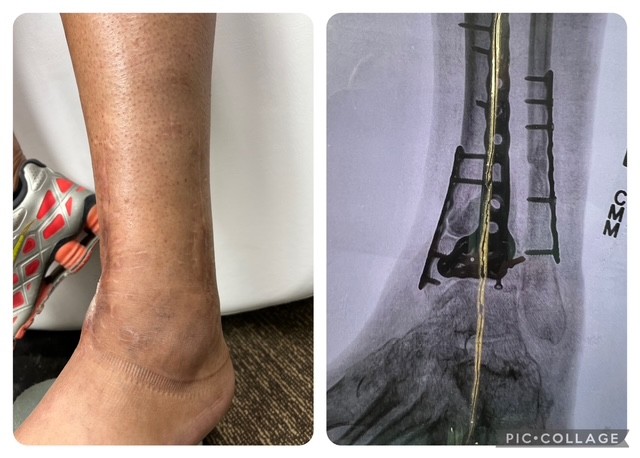

Cryotherapy isn’t new in sports recovery — it’s just new here! 💨✨ Don’t wait to experience it for yourself… the longer you put it off, the longer your recovery takes! 💪❄️ ❄️ Recover Faster with Localized Cryotherapy! Dealing with an ankle injury? Localized cryotherapy targets the exact area of pain reducing inflammation, easing soreness, and speeding up recovery🦵✨ Unlike traditional icing, this quick, targeted treatment penetrates deeper and works faster—so you can get back on your feet in no time! 💙 Fast relief 💙 Reduced swelling 💙 Enhanced recovery

đź§Š Titanium is cryo-safe Titanium is non-magnetic and highly temperature-stable, so it does not react negatively to cryotherapy temperatures when properly healed.